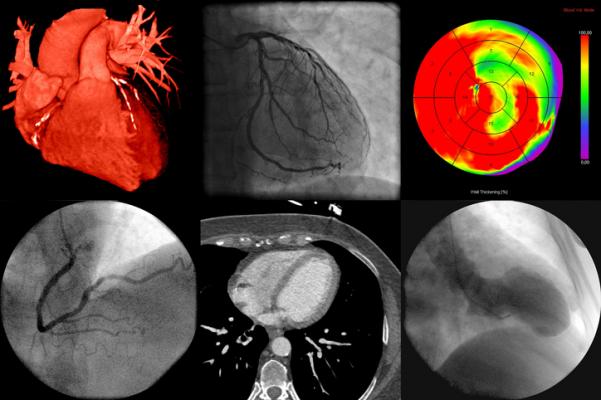

Imaging has long played a critical role in the diagnosis of cardiovascular disease, the leading killer in the world. Both radiologists and cardiologists perform noninvasive cardiac imaging, but over time two of the most common cardiac imaging methods, echocardiography and myocardial perfusion imaging, became almost exclusively the domain of cardiologists.

During that same period, technological advances made competing imaging exams traditionally performed by radiologists, such as cCTA, appealing options.

Over the same period, the rates of cCTA by radiologists in hospital outpatient departments increased by 355%. Overall rates, however, remained low compared to myocardial perfusion imaging, despite the fact that some studies have shown cCTA to be more accurate. The technology’s uptake may be limited, Reeves said, by its complexity and the cost of equipment, in addition to the fact that it requires a dedicated technologist.

Still, he said, the increasing rate of cCTAs performed by radiologists represents a growing opportunity for collaboration in cardiac imaging. Recently at Thomas Jefferson, cardiologists have shown interest in reading cCTA exams side-by-side with radiologists to enhance patient care.

“Coronary CTA is a useful screening tool for coronary artery disease that obviates the need for invasive coronary angiography,” Reeves said. “I think the future is looking favorably on it.”